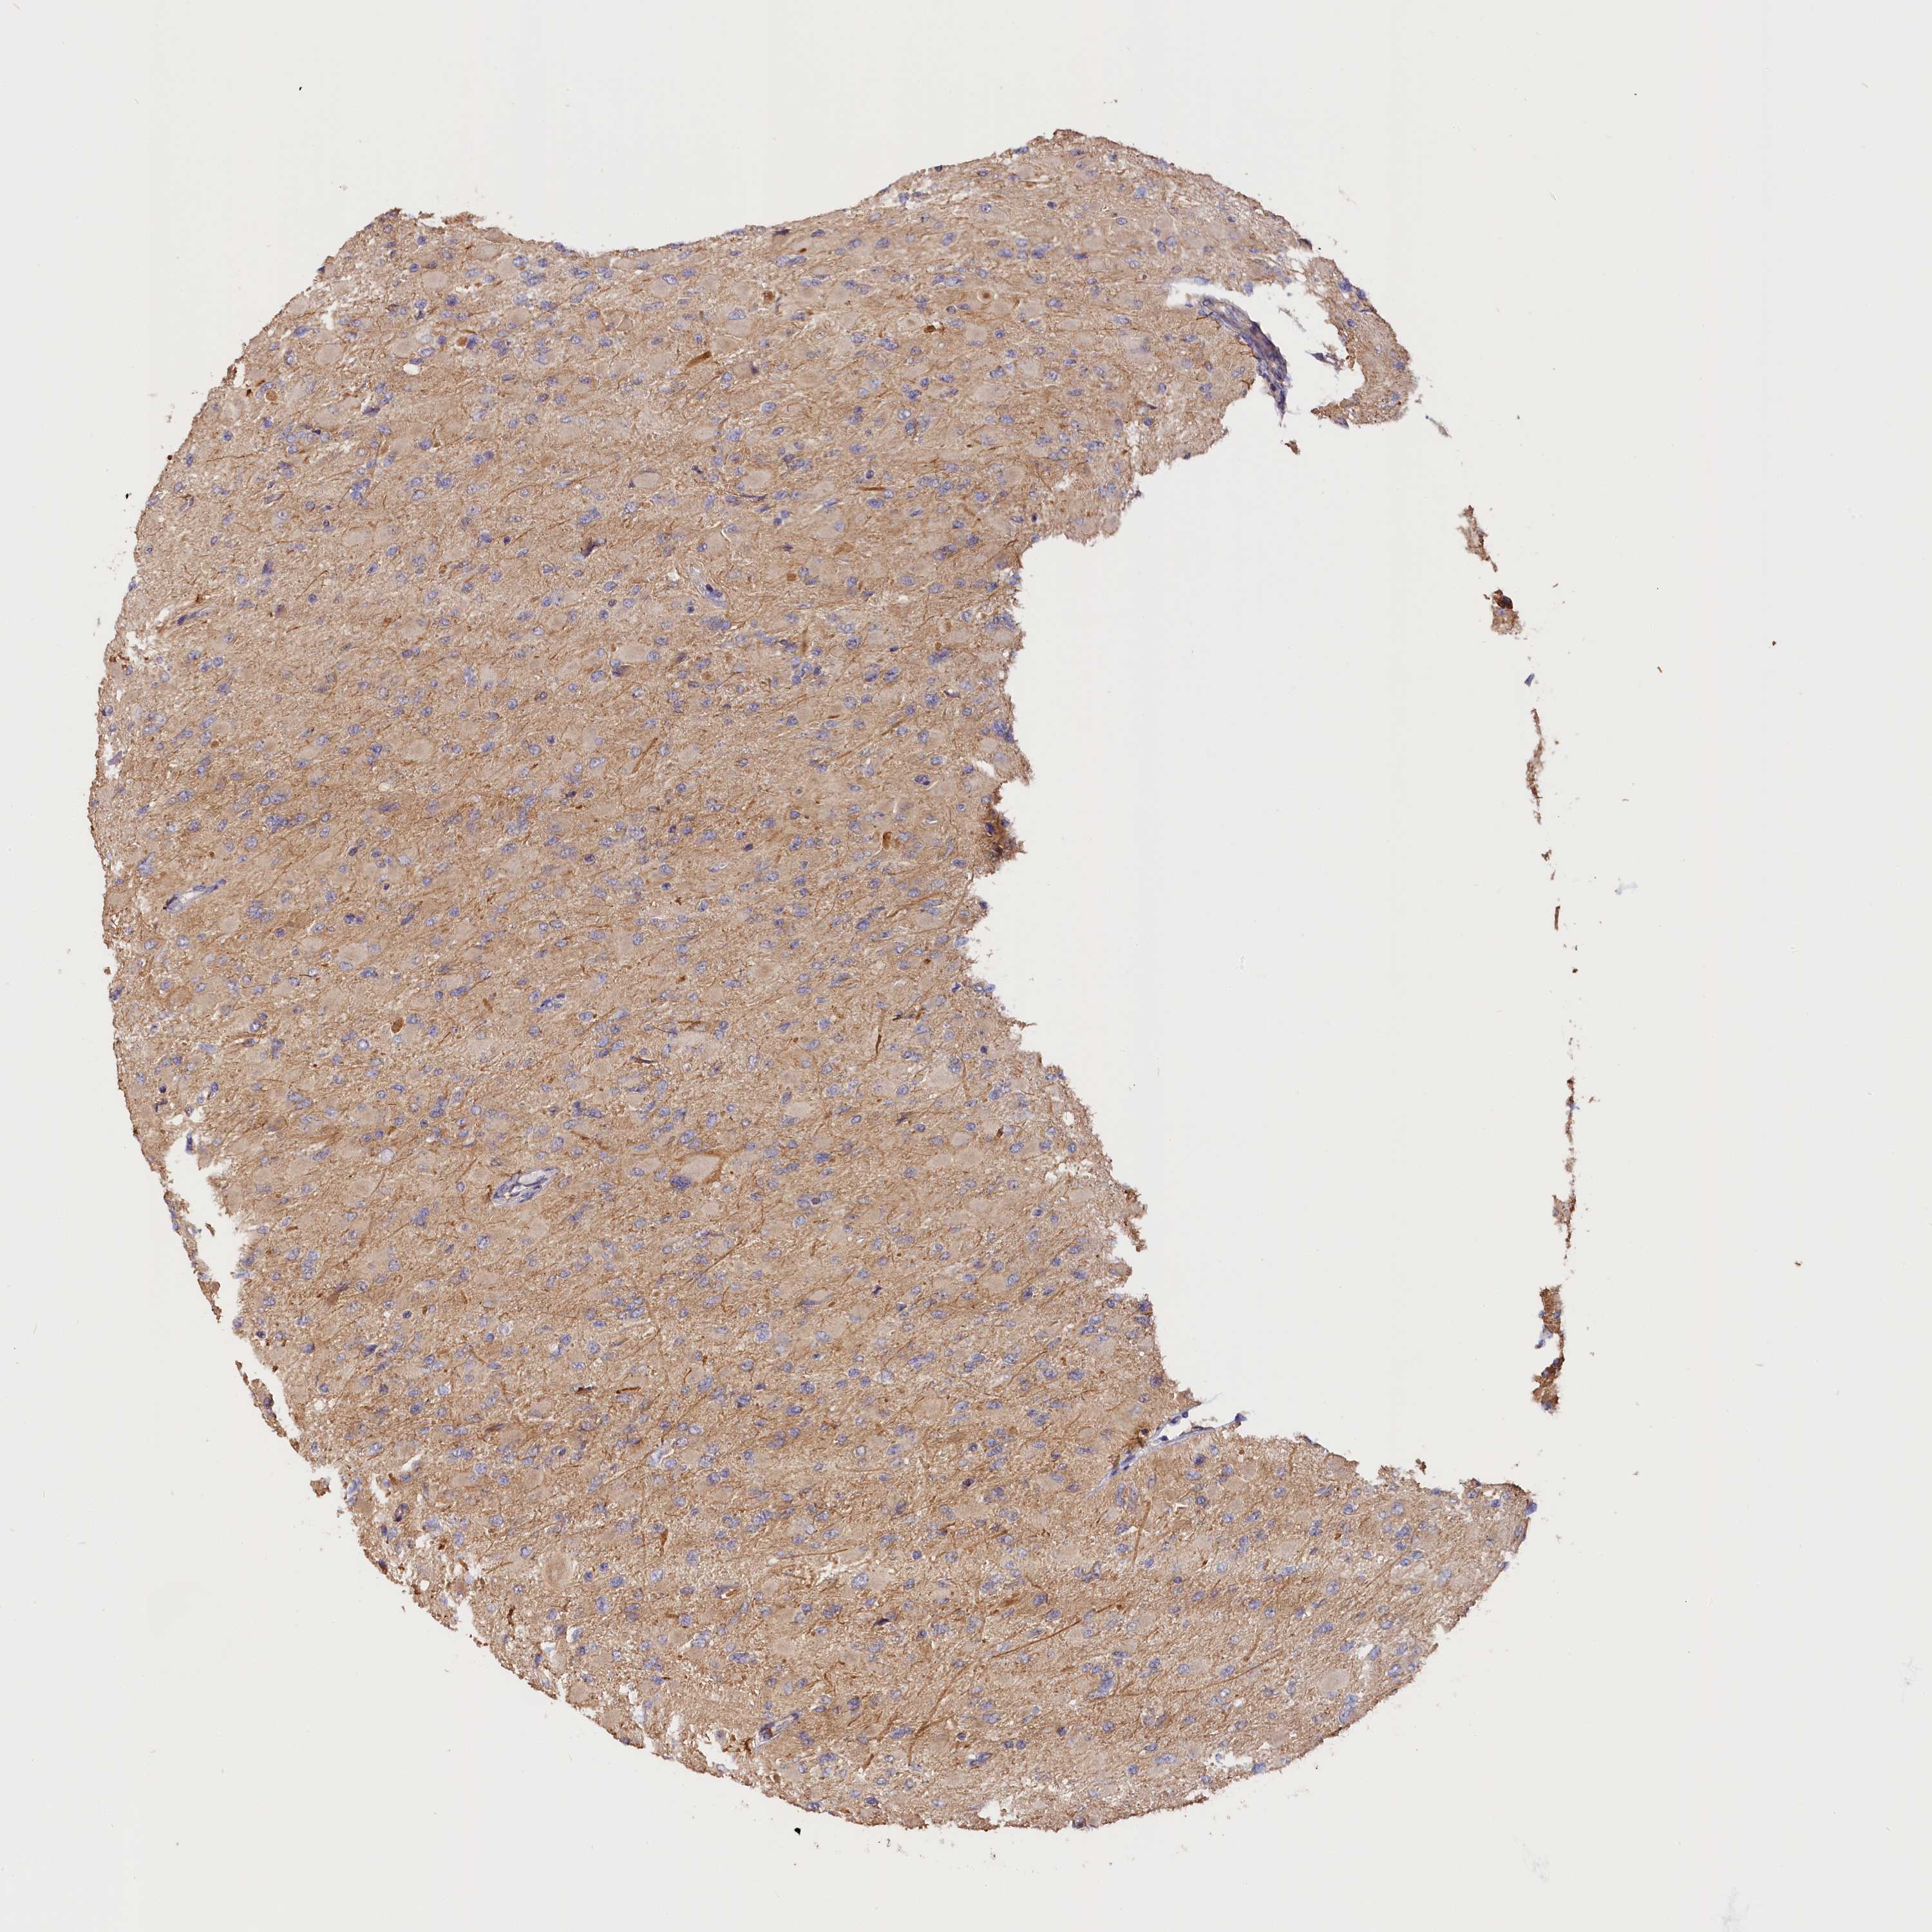

GLIOMA - Protein expressioni

A mouse-over function shows sample information and annotation data. Click on an image to view it in a full screen mode. Samples can be filtered based on level of antibody staining by selecting one or several of the following categories: high, medium, low and not detected. The assay and annotation is described here.

Note that samples used for immunohistochemistry by the Human Protein Atlas do not correspond to samples in the TCGA dataset.

Antibody stainingi

Antibody staining in the annotated cell types in the current human tissue is reported as not detected, low, medium, or high, based on conventional immunohistochemistry profiling in selected tissues. This score is based on the combination of the staining intensity and fraction of stained cells.

Each image is clickable and will lead to virtual microscopy that enables deeper exploration of all samples and also displays staining intensity scores, fraction scores and subcellular localization as well as patient and tissue information for each sample.

Antibody HPA041165

Antibody HPA041839

Staining

High

Medium

Low

Not detected

Intensity

Strong

Moderate

Weak

Negative

Quantity

>75%

75%-25%

<25%

None

Location

Nuclear

Cytoplasmic/membranous

Cytoplasmic/membranous,nuclear

Glioma, malignant, High grade

Glioma, malignant, Low grade